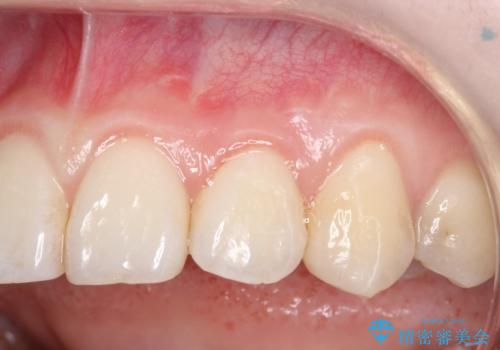

前歯の歯肉退縮 歯周形成外科(歯冠側移動術)